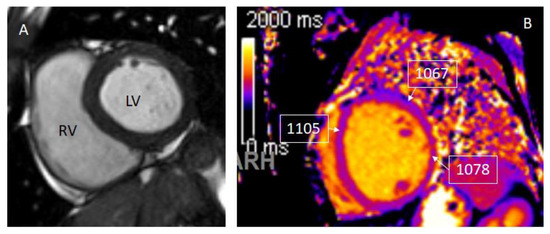

- Messroghli, D.R.; Moon, J.C.; Ferreira, V.M.; Grosse-Wortmann, L.; He, T.; Kellman, P. Clinical recommendations for cardiovascular magnetic resonance mapping of T1, T2, T2* and extracellular volume: A consensus statement by the Society for Cardiovascular Magnetic Resonance (SCMR) endorsed by the European Association for Cardiovascular Imaging (EACVI). J. Cardiovasc. Magn. Reson. 2017, 19, 75. [Google Scholar] [PubMed] [Green Version]

- Hinojar, R.; Foote, L.; Ucar, E.A.; Jackson, T.; Jabbour, A.; Yu, C.-Y.; mcChohon, J.; Higgins, D.M.; Carr-White, G.; Mayr, M.; et al. Native T1 in discrimination of acute and convalescent stages in patients with clinical diagnosis of myocarditis: A proposed diagnostic algorithm using CMR. JACC Cardiovasc. Imaging 2015, 8, 37–46. [Google Scholar] [CrossRef] [Green Version]

- Bohnen, S.; Radunski, U.K.; Lund, G.K.; Kandolf, R.; Stehning, C.; Schnackenburg, B.; Adam, G.; Blankenberg, S.; Muellerleile, K. Performance of T1 and T2 mapping cardiovascular magnetic resonance to detect active myocarditis in patients with recent-onset heart failure. Circ. Cardiovasc. Imaging 2015, 8, e003073. [Google Scholar] [CrossRef] [Green Version]

- Cornicelli, M.D.; Rigsby, C.K.; Rychlik, K.; Pahl, E.; Robinson, J.D. Diagnostic performance of cardiovascular magnetic resonance native T1 and T2 mapping in pediatric patients with acute myocarditis. J. Cardiovasc. Magn. Reson. 2019, 21, 40. [Google Scholar] [CrossRef] [PubMed] [Green Version]